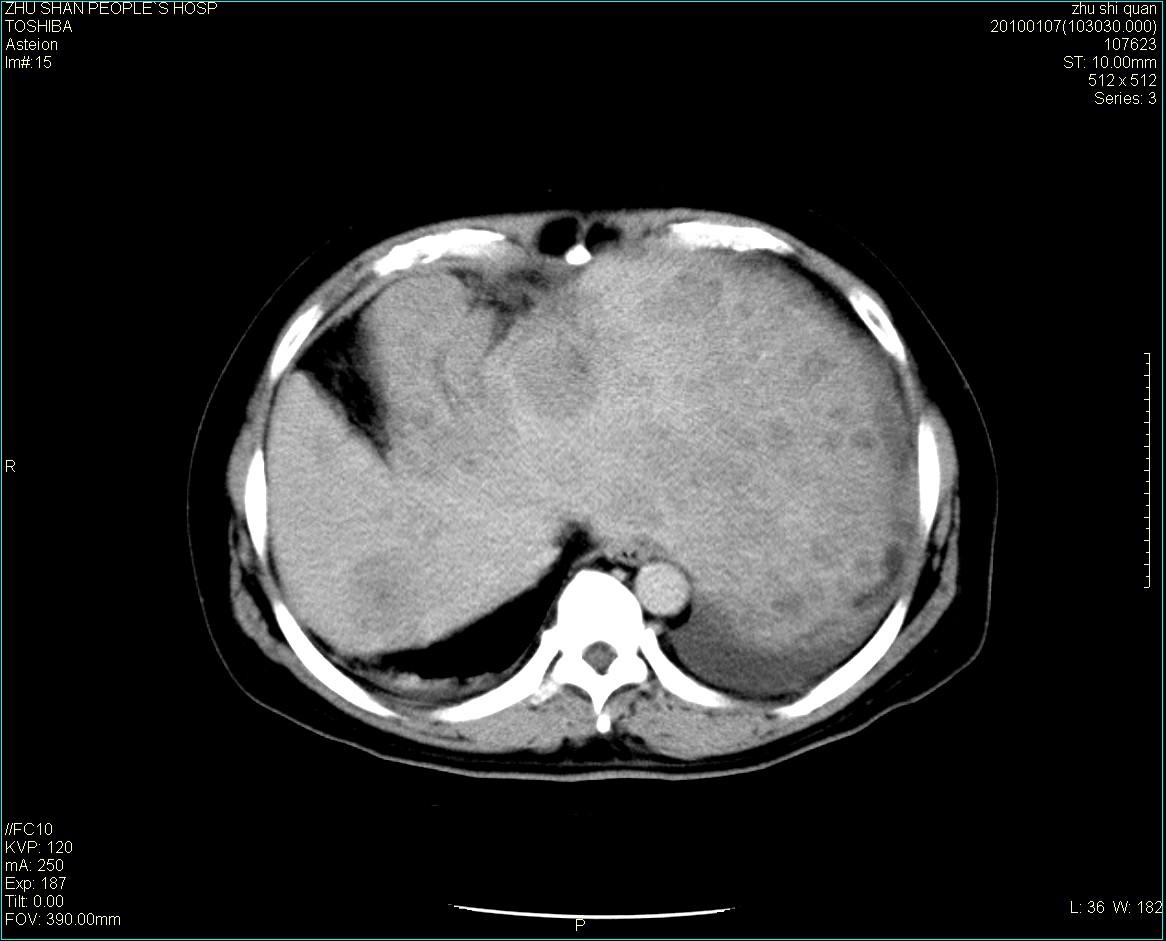

男性病人 肝ca两次术后,今日复查。

多发转移

肝、脾多发转移灶,胸腔积液

多发转移灶

1)肝癌并多发性转移。2)双侧胸腔积液(以左侧为甚)伴左下部分肺萎陷。

肝癌术后复发,考虑肝、脾多发转移。

肝癌术后复发,肝内、脾脏、腹膜后及腹膜多发转移,腹水,双侧胸腔积液(以左侧为甚)伴左下膨胀不全。

肝、脾多发转移灶,胸腔积液。

肝癌术后复发,肝内、脾脏、腹膜后及腹膜多发淋巴结转移,腹水,双侧胸腔积液。